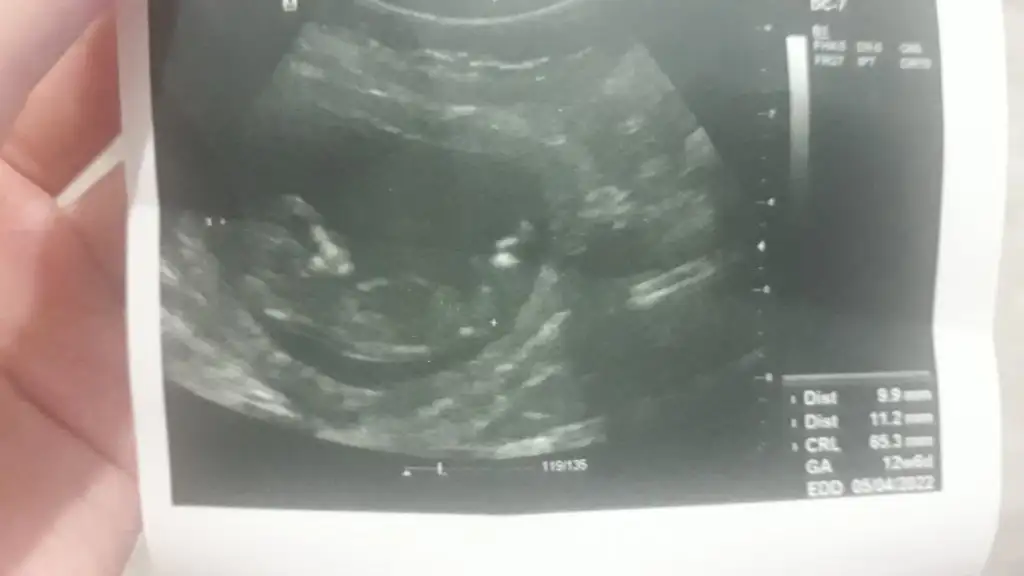

Merhaba bana da tahmin yapabilir misiniz 12+1 günlük Ikra meyra Ikra meyra